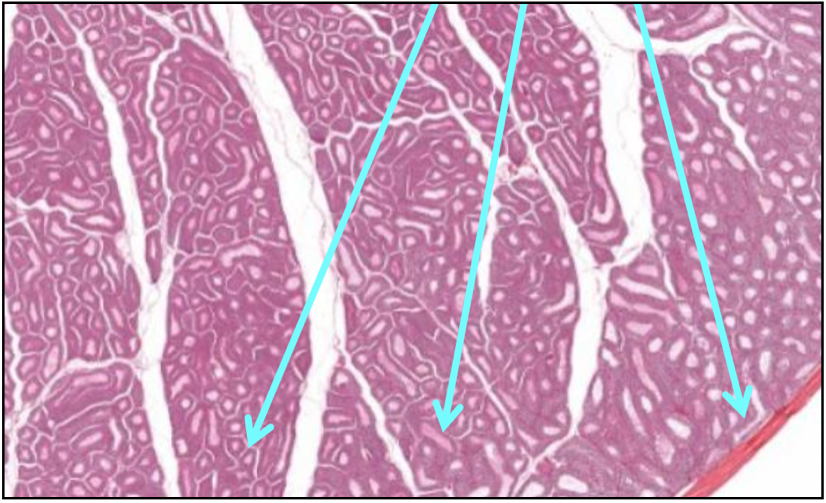

What is shown in this image?

The Testis-testicular lobules

What does the arrows in this image show?

Semoniferous Tubules